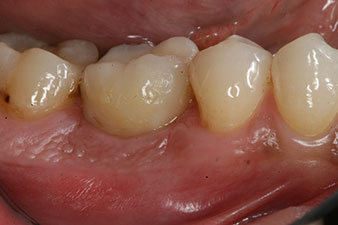

Nach Abheilung der Weichgewebe wurde vor der weiteren prothetischen Versorgung die Implantatstabilität erneut bestimmt.

Beide Werte waren praktisch unverändert und lagen im Übergang vom mittleren in den hohen Bereich – wobei der niedrigere Wert immer als therapiebestimmende Referenz dient.

Damit konnten eine erfolgreiche Osseointegration und ausreichende biologische Stabilität dokumentiert werden, die eine Abformung in derselben Sitzung erlaubte.

Die Abschlussbilder zeigen die verschraubte monolithische Kompositkrone in situ und die Röntgenkontrolle (Abb. 9 und 10) (6).